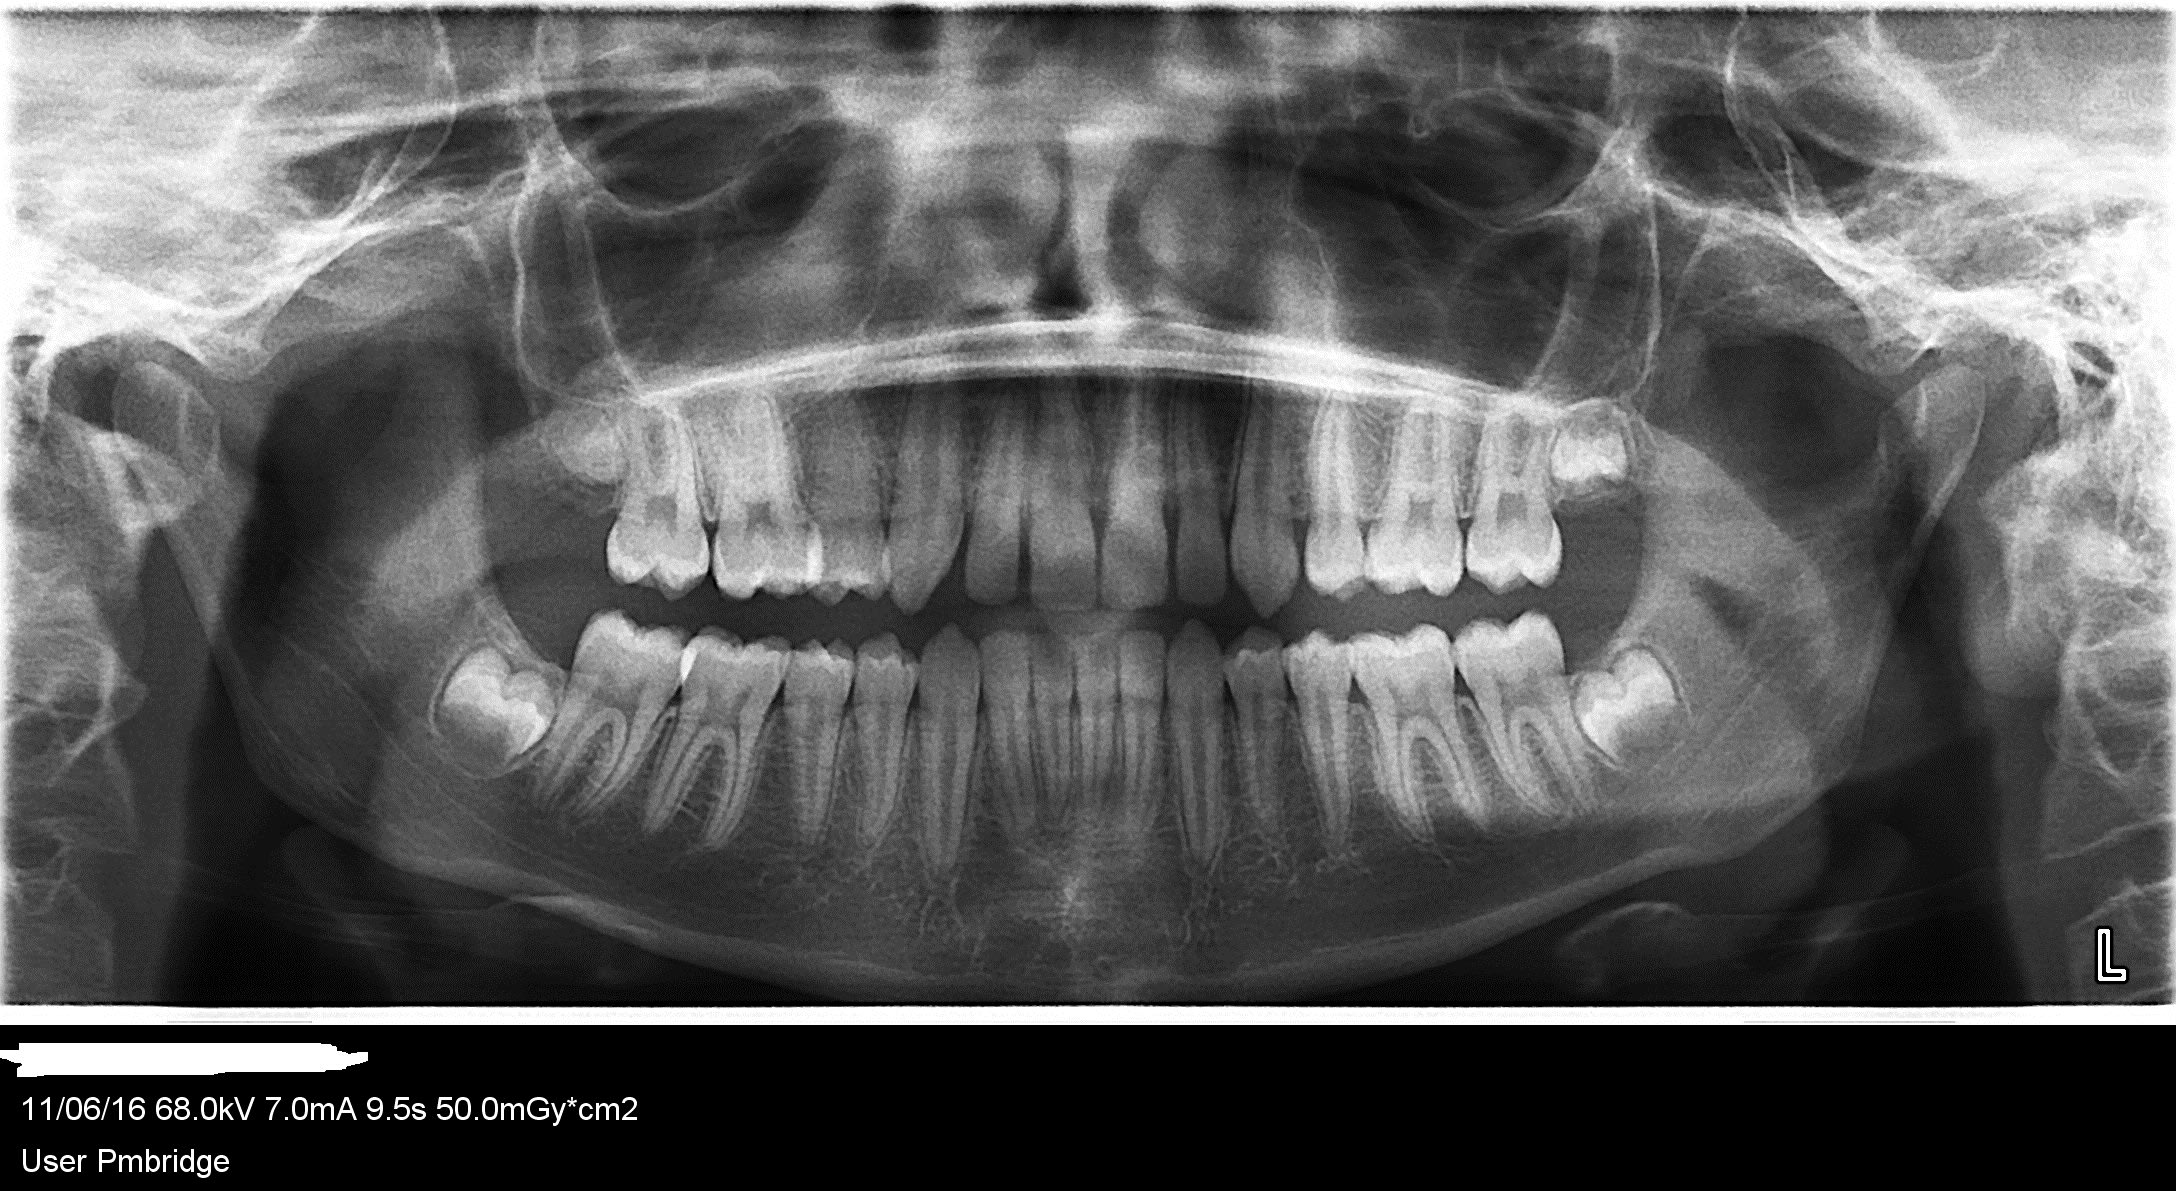

En recherchant pourquoi ce jeune patient de 17 ans avait mal après le repas, le soir à sa 16, j'ai vu cette tache radio claire au sinus droit, contre l'orbite, qui a augmenté en 3 ans. Est ce que qq'1 peut l'interpréter? merci d'avance

En regardant bien cette 16, on voit un sillon radio opaque, certainement obturé a l'oxyde de zinc , sillon qui se dirige vers la pulpe, ce genre de lésion assez rare que tu as bien traité, mais qui existe avec un pronostic souvent sombre pour la conservation de la vitalité a tres long terme.

Une retro serait bien pour confirmer ; ta pano est de tres bonne qualité.

Probable carie en mésial de cette 16. Une rétro ?

on dirait que la chambre pulpaire de la 16 contient plus de pulpolithes qu'il y a 3 ans.

Ca signe la souffrance pulpaire.

Le test de morsure étant positifi surement fissure, avec/sans carie.

dent peut etre partiellement nécrosée comme disait adhoc.

A moins d'un artefact, tu as une belle zone radio claire sur distal de 17... A reprendre avec un autre centrager si possible....A cet age, on ne s'y attend pas, mais ca arrive....

et bien déjà un cone beam à ce niveau. Ce peut être un artefact radio, perso je deteste les panos car sont toujours très déformés et pleines d'image fantôme. Ceci étant dit tu dois faire u compte rendu et le noter puis adresser pour vérification. Si c'est rien on ne te reprocheras rien, si tu fais pas et que c'est une merde, t'nquiètes, on sauras te trouver.

La pano permet d'avoir une vue globale mais pas beaucoup plus !!

Un prof nous disait " une pano, ça sert à compter les dents".